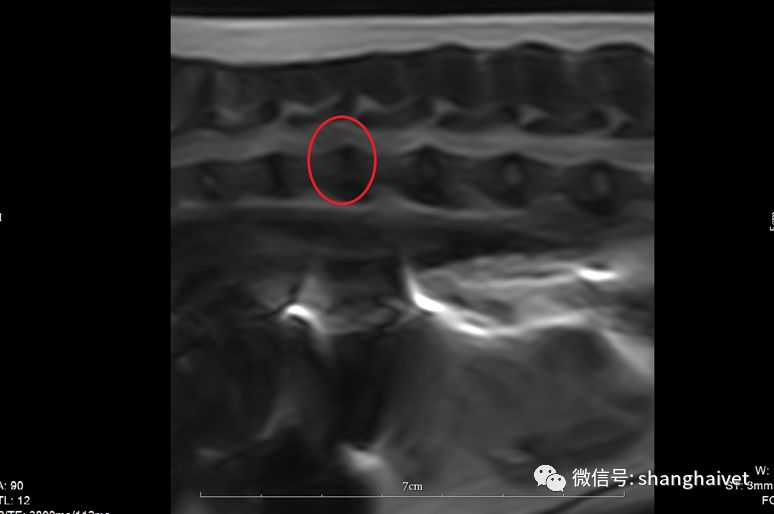

▲MRI扫描显示T12-T13椎间盘信号下降,有突出,且压迫脊髓

进一步的核磁检查显示T12-T13段椎间盘T2信号降低,有较明显的椎间盘突出,压迫脊髓硬膜囊。脊髓本体信号轻度增强,横断面见突出物偏右侧对脊髓造成较明显的压迫。

▲T12-T13横断面 右侧椎间盘突出压迫脊髓